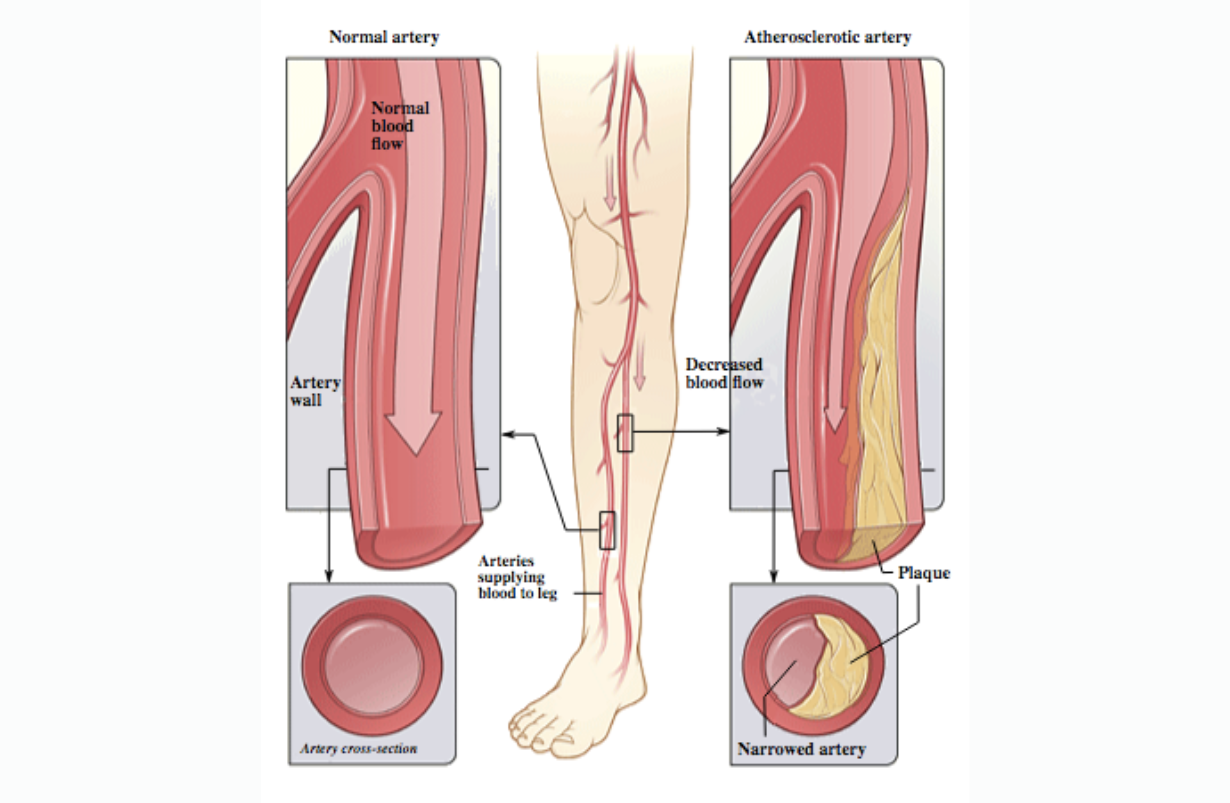

Arterial Peripheral Vascular Disease

Narrowing of the arterial vessels, usually in the lower extremities. This restricts the blood flow, and in even mild or moderate exercise, muscles may require more oxygen than these blood vessels can carry to them. That will result in an inadequate blood supply, or ischemia, which is often painful. This condition is quite predictable. People with arterial insufficiency will often have calf and leg cramps after walking a specific distance, and feel it each time they do so, a condition called intermittent claudication, or pseudo sciatica. One good conservative means of reducing this condition is to reduce the arterial pressure even further, for short periods of time, which will tend to dilate the arterial vessels, and induce more collateral circulation. Headstand is a fine way to do this. Another effective conservative method is to walk as far as possible (before serious pain develops), then stop, and then return home. Doing this daily will double the walking range every three months. It is critical to avoid cuts in the feet and toes, since the healing process raises the blood flow demands, and infection will sometimes raise them so high above the actual ability of the maximum arterial supply that gangrene will follow.